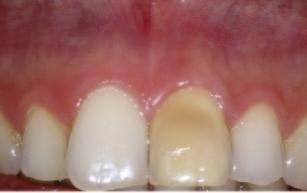

A 30-year-old patient presented to your clinic complaining of a discoloured front tooth (Figures 1 and 2). There was no pain or other symptoms associated with it and it has become increasingly discoloured over time.

1. What is the likely reason for this type of discolouration?

2. What special tests do you perform as part of your exam?

3. What are the potential sequalae for this tooth?

4. What are the possible treatment options for

this tooth and what are the potential difficulties with doing a root canal treatment?

Answers on page 45.

FIGURE 1: Patient presenting with discoloured front tooth. FIGURE 2: Periapical radiograph 1.